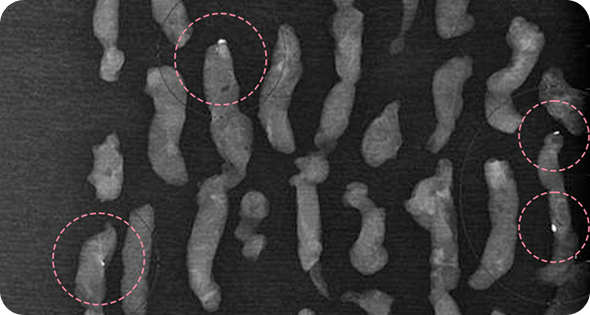

매우 빠르게 자라는 유방 종양 수술을 위해

외국에서 내원한 17세 환자의 사례입니다.

3cm 이상의 유방 종양은 외과적 수술로 제거하는 것이

원칙이고, 대부분의 경우 대학병원으로 연계됩니다.

그러나 한송이 원장은 대학병원에서의 고난도 시술 경력을

다수 보유하고 있어 크기가 큰 종양도 맘모톰 시술로 가능하였습니다.

3번에 걸쳐 맘모톰시술을 시행한 결과 성공적으로 제거를 마칠 수 있었습니다. 외과적 절제로 생길 수 있었을 흉터를 원치 않으셨던 환자와 보호자분 모두 시술 결과에 만족하셨습니다. 매년 추적 검사를 시행하고 있으며, 깨끗이 제거된 상태를 잘 유지하는 중입니다.